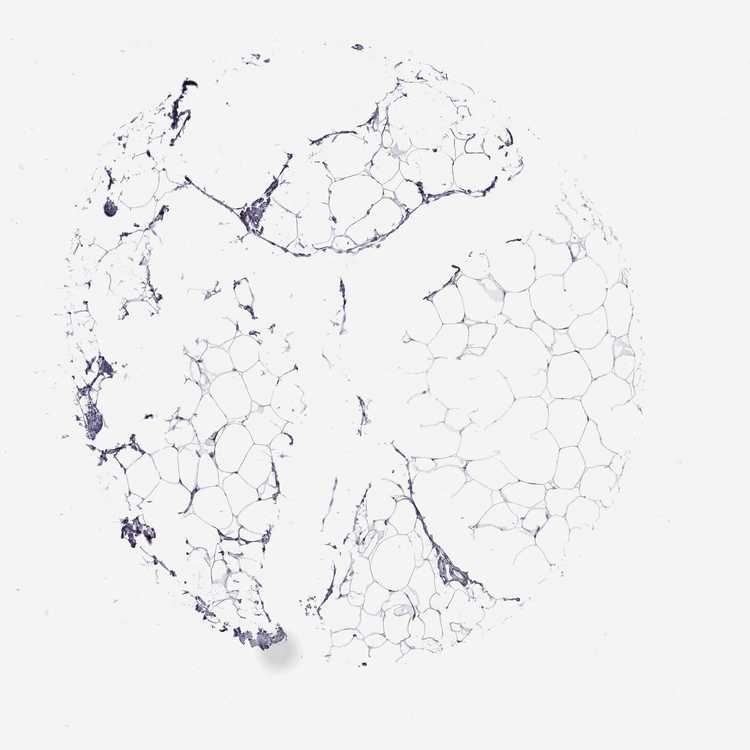

ADIPOSE TISSUE - Antibody stainingi

Antibody staining in the annotated cell types in the current human tissue is reported as not detected, low, medium, or high, based on conventional immunohistochemistry profiling in selected tissues. This score is based on the combination of the staining intensity and fraction of stained cells.

Each image is clickable and will lead to virtual microscopy that enables deeper exploration of all samples and also displays staining intensity scores, fraction scores and subcellular localization as well as patient and tissue information for each sample.

Antibody HPA057790

Adipocytes Not detected